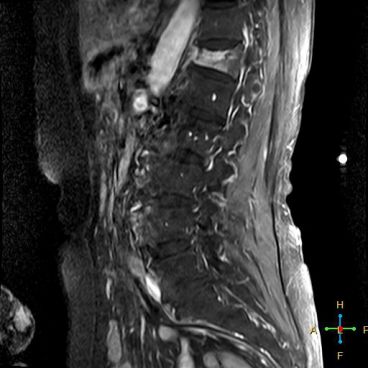

3 恶性压缩性骨折 椎体上下径变窄而前后径增大,椎体后部皮质后突,后角一般表现圆钝,无上翘,常呈球形突出,致椎管狭窄,即膨胀性盘状破坏,硬膜囊和脊髓受压。

——恶性压缩性骨折MR信号特点—— 由于肿瘤组织的侵犯,T1WI上椎体呈弥漫性低信号,T2WI呈高信号,增强扫描呈明显不均匀强化。

转移瘤 椎弓根改变:椎弓根膨大仅见于恶性压缩性骨折,故为其特异性,可作为鉴别诊断的依据。

椎旁软组织肿块:在转移瘤中,受累椎体周围多出现分叶状或肿瘤样软组织肿块,此征象仅见于恶性压缩性骨折。故,椎旁薄环状软组织与瘤样软组织肿块是鉴别骨折性质较有特征性的征象。

——恶性压缩性骨折—— 扁平形或倒楔形 跳跃性分布(转移瘤) 椎间盘不受累 T1WI均匀低信号 后角圆钝,膨胀性盘状破坏 椎弓根受累、膨大 椎旁分叶状及肿瘤样软组织肿块